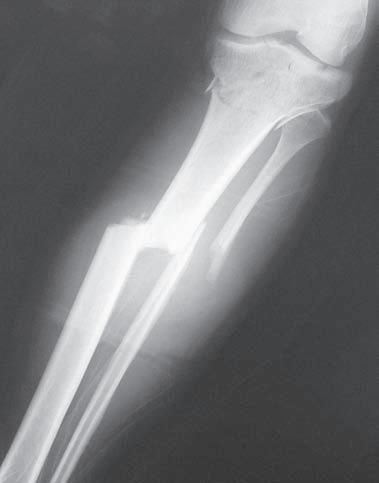

Obr. 2.1 Jednoduchá příčná zlomenina tibie, typ A podle AO klasifikace. Současně je přítomná nedislokovaná nitrokloubní zlomenina proximální části

Obr. 2.2 Spirální zlomenina distální části tibie a šikmá zlomenina zevního kotníku. Typ A podle AO klasifikace